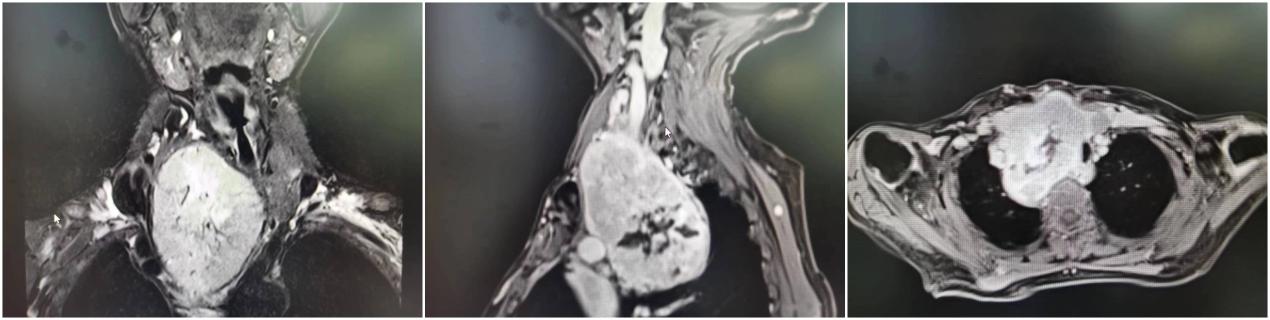

安媛主任医师详细了解病史并查体后,将刘大娘收治入院。经检查发现,刘大娘颈部的重要血管、神经都受到侵犯和压迫,上腔静脉综合症症状明显,纵隔、肺门、腋窝淋巴结肿大,并骨转移。诊断为:甲状腺恶性肿瘤IV B期,患者瘦弱,又合并高血压、类风湿性关节炎、双肺支气管肺炎等基础疾病。

安媛主任医师带领头颈外科一组治疗团队在综合评估患者病情后,认为患者病情危重,并上报医务部。医务部专门组织了全院MDT(多学科讨论),会上,专家们一致认为患者病灶巨大,压迫症状明显,也无有效的非手术治疗方案,如不手术,患者将面临死亡风险。为此,影像科专家详细解读了患者CT和磁共振成像,为外科专家们制定手术方案提供参考。头颈肿瘤外科与胸部肿瘤外科专家确定了手术可行性,决定为患者行“颈胸联合劈胸入路胸骨后甲状腺巨大肿瘤根治切除手术”,并制定了详细的手术方案。

胸骨后巨大甲状腺肿瘤为高风险四级手术,受手术方案及术中出血等多方面因素影响,术中如果出现上腔静脉破裂,极有可能造成不可挽救的致命性大出血。为此,手术前,输血科多方协调,为患者准备了充足的血液,保障手术安全。经过充分的术前准备,在麻醉科的保驾护航下,头颈外科安媛主任医师团队、胸外科宋养荣主任医师团队戮力合作为刘大娘进行手术。术中见病灶填满上纵膈,颈鞘、头臂干、上腔静脉等重要组织,手术团队仔细分离,保护了上述重要器官和组织,摘除过程犹如抽丝剥茧。经过6小时的努力,终于成功剥离一直径约10厘米的巨大肿块。